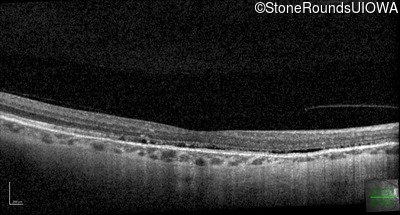

Optical Coherence Tomography - Right - 20/20 -3 sc

Exemplar / OCT Stack

OCT Stack